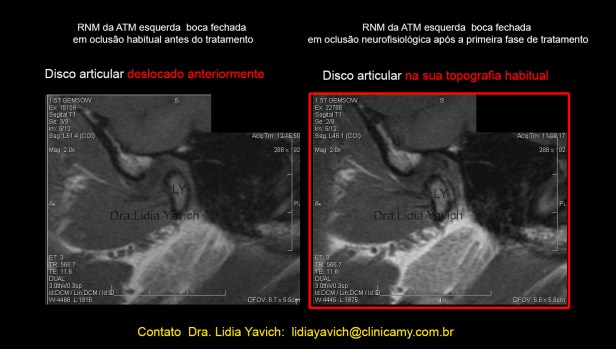

RNM: Ressonância Nuclear Magnética do paciente. Corte selecionado.

1 corte sagital da ATM ESQUERDA em boca fechada antes do tratamento. Deslocamento redutivel do disco articular.

2 -A mesma imagem com realce de cores.

3 -corte sagital da ATM ESQUERDA em boca aberta antes do tratamento.

4– A mesma imagem com realce de cores.  RNM: Ressonância Nuclear Magnética do paciente. Corte selecionado. Corte sagital da ATM DIREITA em boca fechada antes do tratamento.

Corte sagital externo da ATM esquerda em boca fechada antes do tratamento mostrando o DESLOCAMENTO DO DISCO ARTICULAR e a RECAPTURA DO DISCO ARTICULAR após o tratamento.

Controle comparativo da segunda ressonância nuclear magnética após a primeira fase do tratamento. Serão postadas as imagens da ATM esquerda, que apresentava o deslocamento do disco articular.

Corte sagital externo da ATM esquerda em boca fechada antes do tratamento mostrando o DESLOCAMENTO DO DISCO ARTICULAR e a RECAPTURA DO DISCO ARTICULAR após o tratamento.

Corte sagital interno da ATM esquerda em boca fechada antes do tratamento mostrando o DESLOCAMENTO DO DISCO ARTICULAR e a RECAPTURA DO DISCO ARTICULAR após o tratamento.

Corte sagital interno da ATM esquerda em boca fechada antes do tratamento mostrando o DESLOCAMENTO DO DISCO ARTICULAR e a RECAPTURA DO DISCO ARTICULAR após o tratamento.